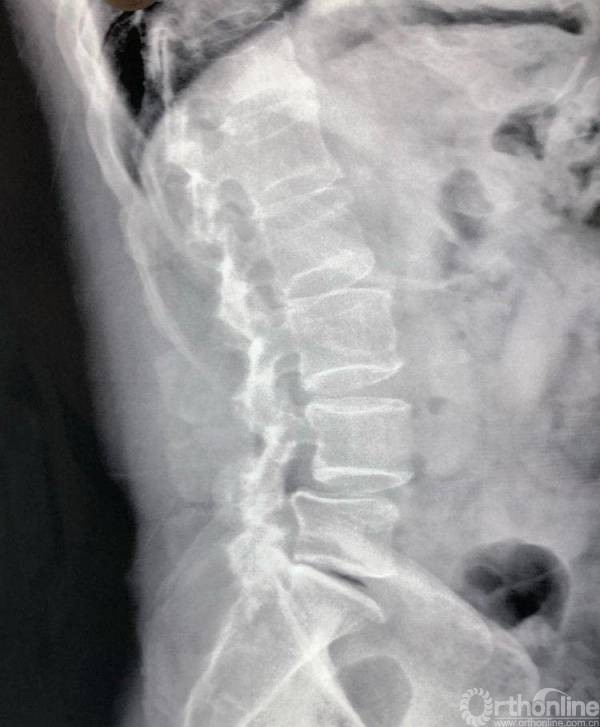

术前CT示L4/5重度椎管狭窄,腰椎滑脱合并硬膜囊受压。辅助检查如下:

过伸位X片